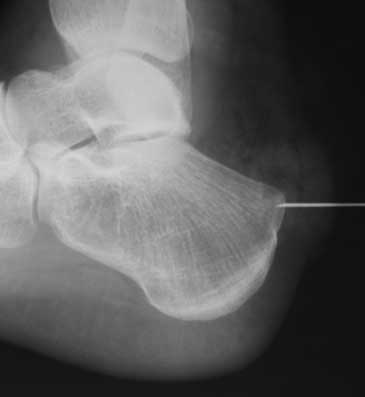

Сегодня прооперировал пациентку. Результат идентичный на обеих ногах, выкладываю одну. Огромное спасибо всем коллегам за помощь.

Юрий Алексеевич Булахтин

Камчатский Военно-морской госпиталь